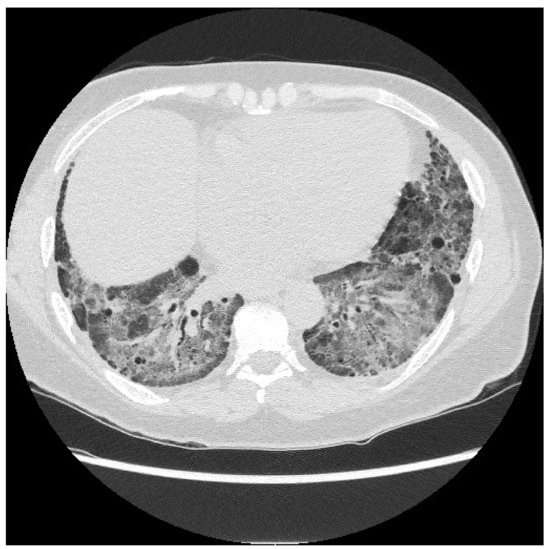

6.2. Histopathologic and Radiographic Findings in Myositis-Associated ILD